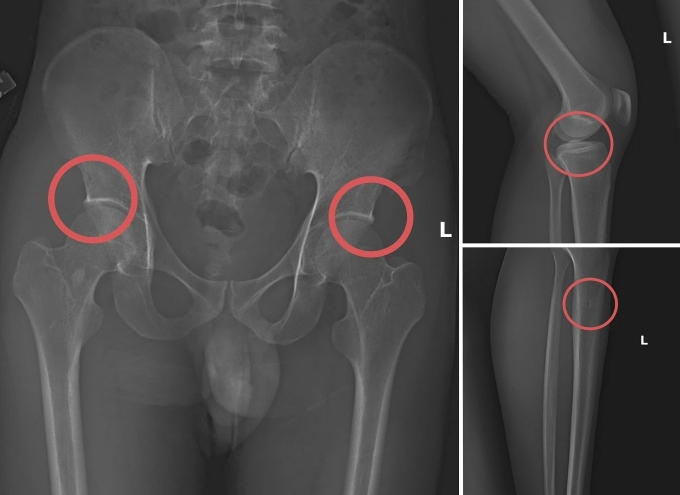

Các vết thương do Châu tự tạo nên. Ảnh: Công an cung cấp

Tại đây, anh ta tiêm thuốc mê vào tĩnh mạch tay phải của người mua bảo hiểm để họ hôn mê. Sau đó, Châu dùng búa và kim tiêm đục, đâm vào vùng cơ thể đã thống nhất từ trước để tạo vết tổn thương trên xương cho nứt, vỡ. Thông thường, Châu sẽ làm rạn nứt, vỡ vùng xương chậu, đùi.